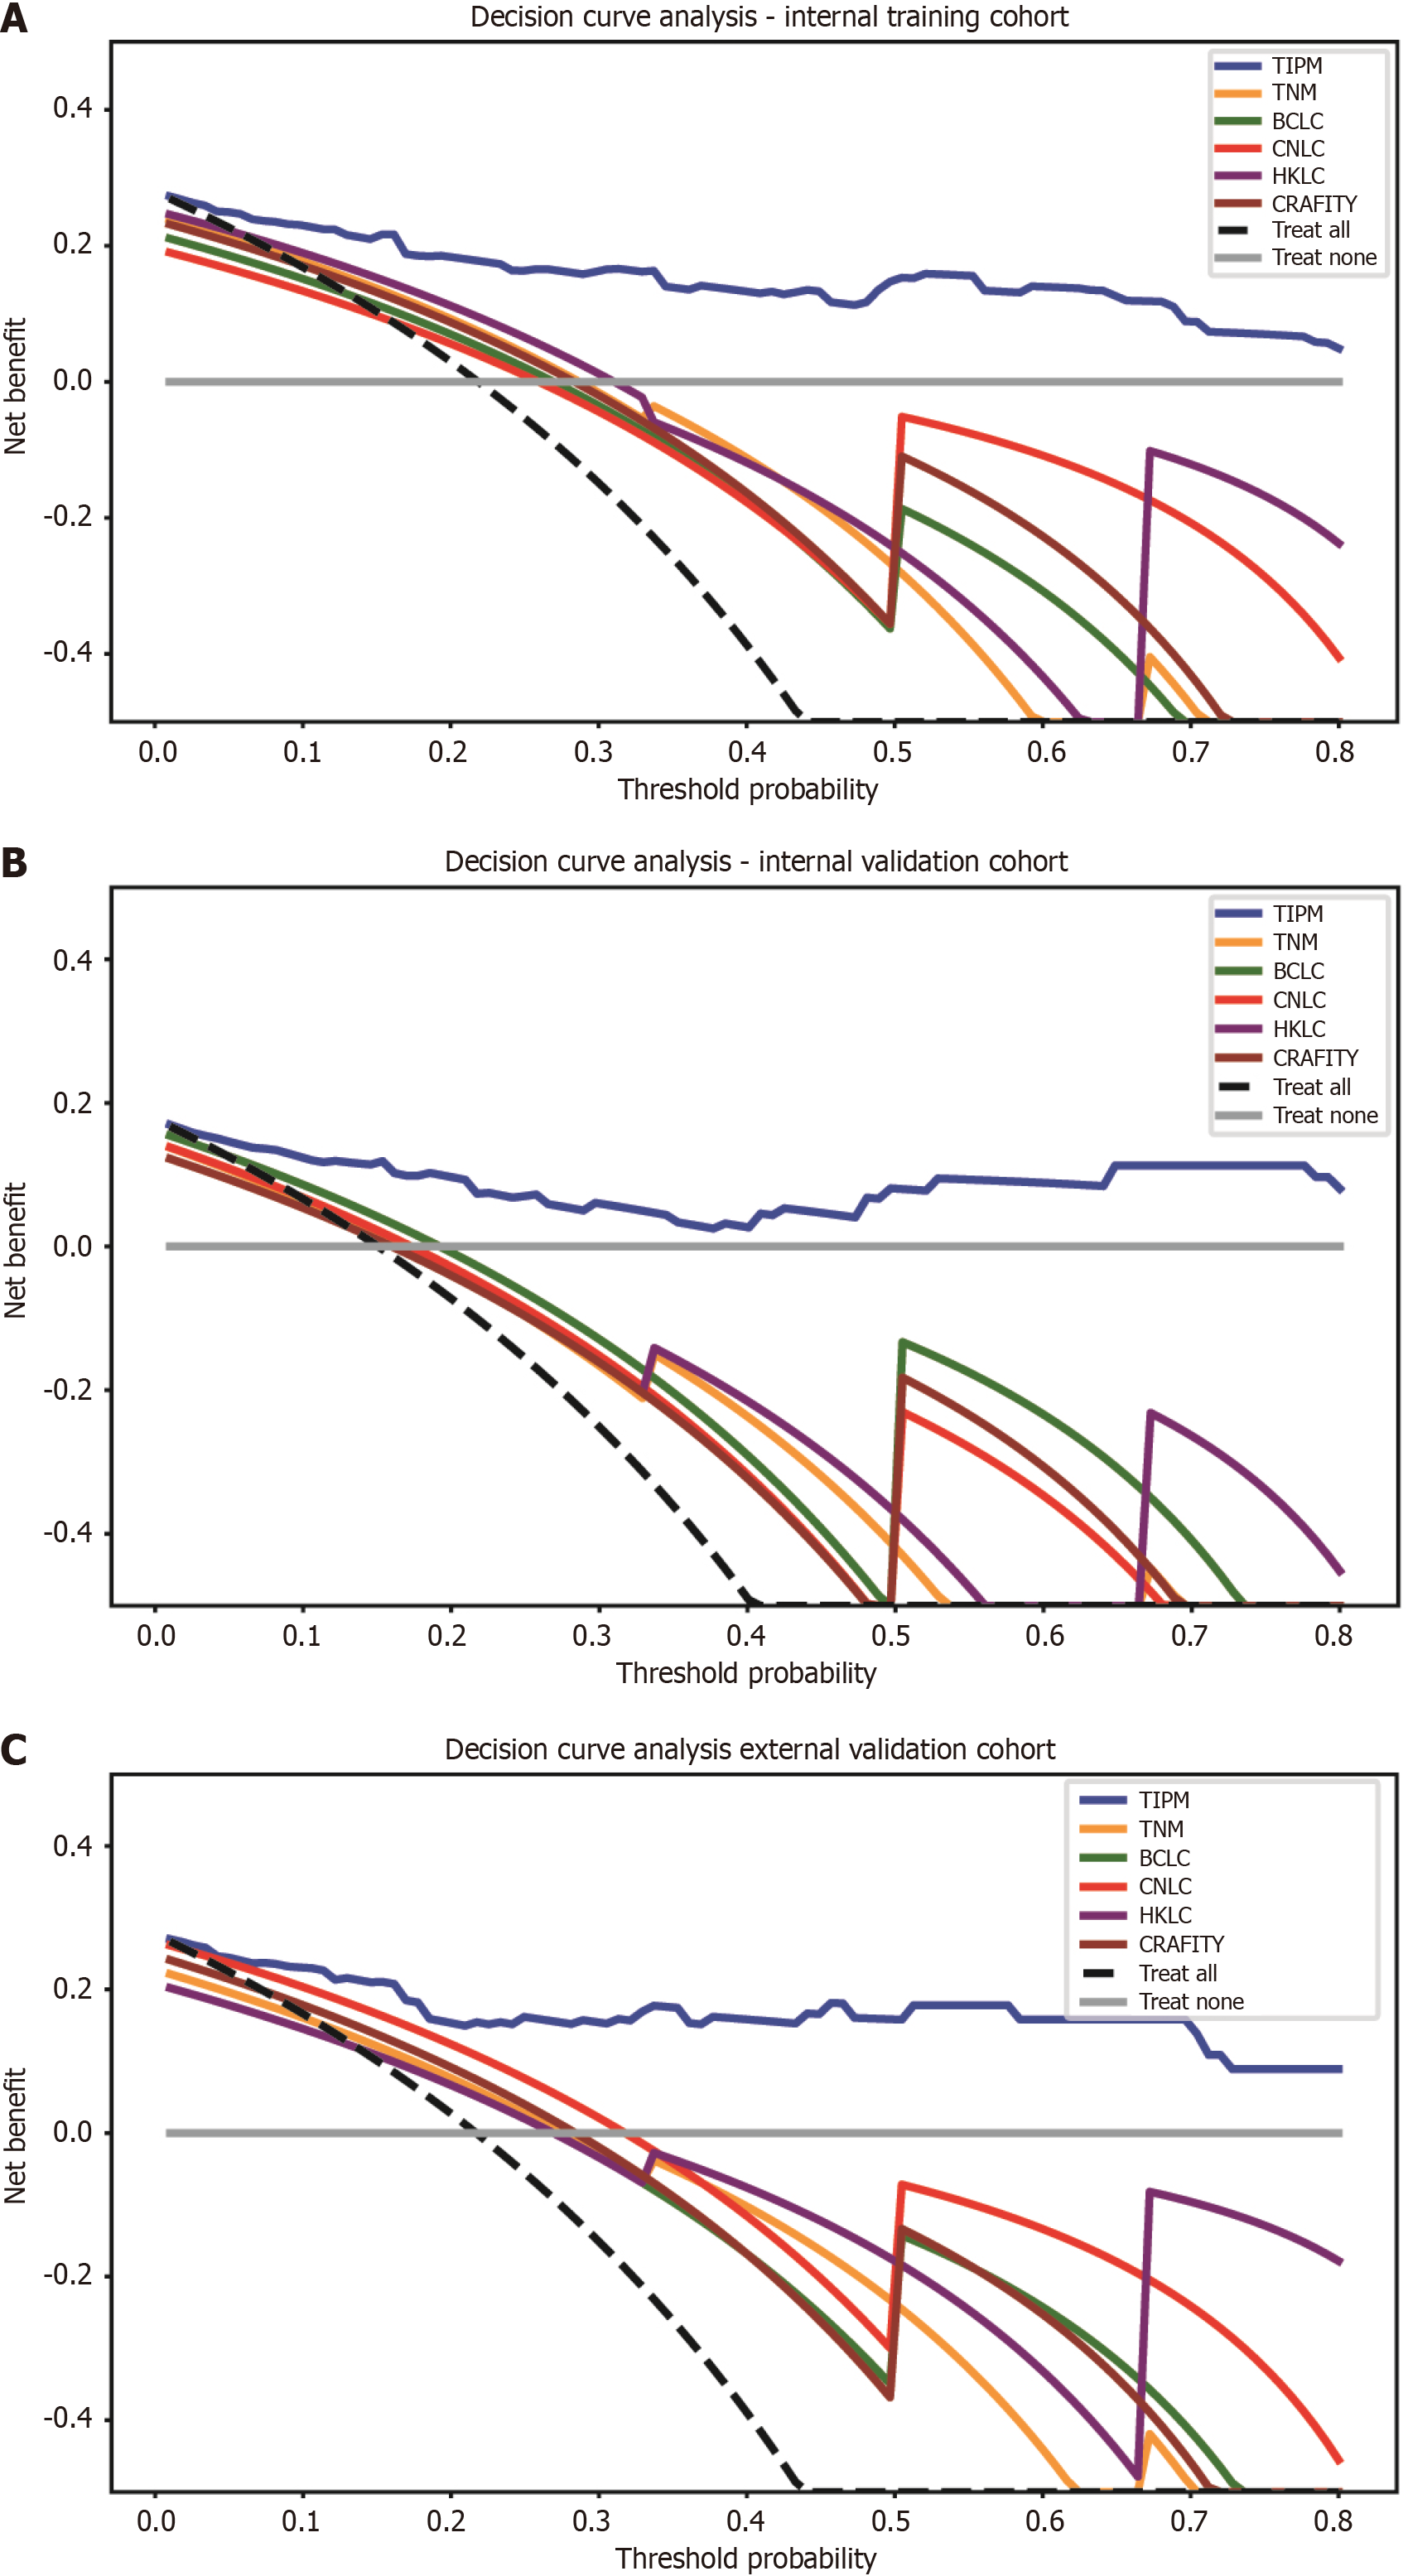

Figure 6 Decision curve analysis for model comparison across cohorts.

A: In the internal training cohort, the Target Immunotherapy Predictive Model (TIPM) is positioned in the upper right corner of the graph, indicating the highest clinical benefit rate; B: In the internal validation cohort, TIPM’s performance slightly decreased compared to the training cohort but remained in the upper right corner; C: In the external validation cohort, TIPM continued to occupy the upper right corner, demonstrating its robust external generalizability. TIPM: Target Immunotherapy Predictive Model; TNM: Tumor-node-metastasis; BCLC: Barcelona Clinic Liver Cancer; CNLC: China Liver Cancer; HKLC: Hong Kong Liver Cancer; CRAFITY: C-reactive protein and alpha-fetoprotein in immunotherapy.